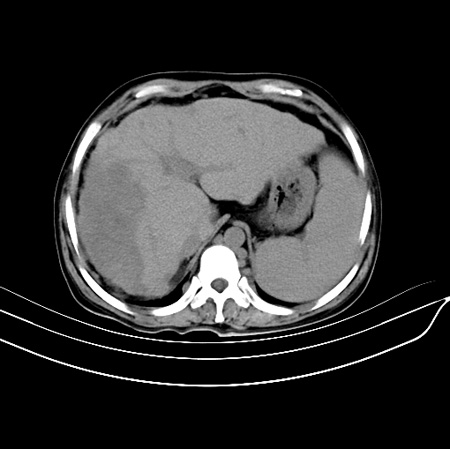

以下是引用江尾海头在2007-9-7 19:01:00的发言:[br]肝叶比例失调,肝边缘高低不平,尾状叶增大,肝裂增宽。肝右叶见较大密度减低影,边缘欠清。脾脏明显增大,胃底及奇静脉半奇静脉曲张。胆囊未见明显显示。 考虑:1、肝癌。2、肝硬化伴脾大静脉曲张。

以下是引用zhangxu5888在2007-9-7 22:31:00的发言:[br]1、肝硬化,食管 胃底及奇静脉半奇静脉曲张;2、脾脏肿大; 3、肝右叶的病灶呈锲性改变,内可见条片状钙化,边界清晰,密度明显低于周围正常肝组织,我觉得肝癌可能性不是很大, 同意楼上观点,有可能是栓塞,建议增强.